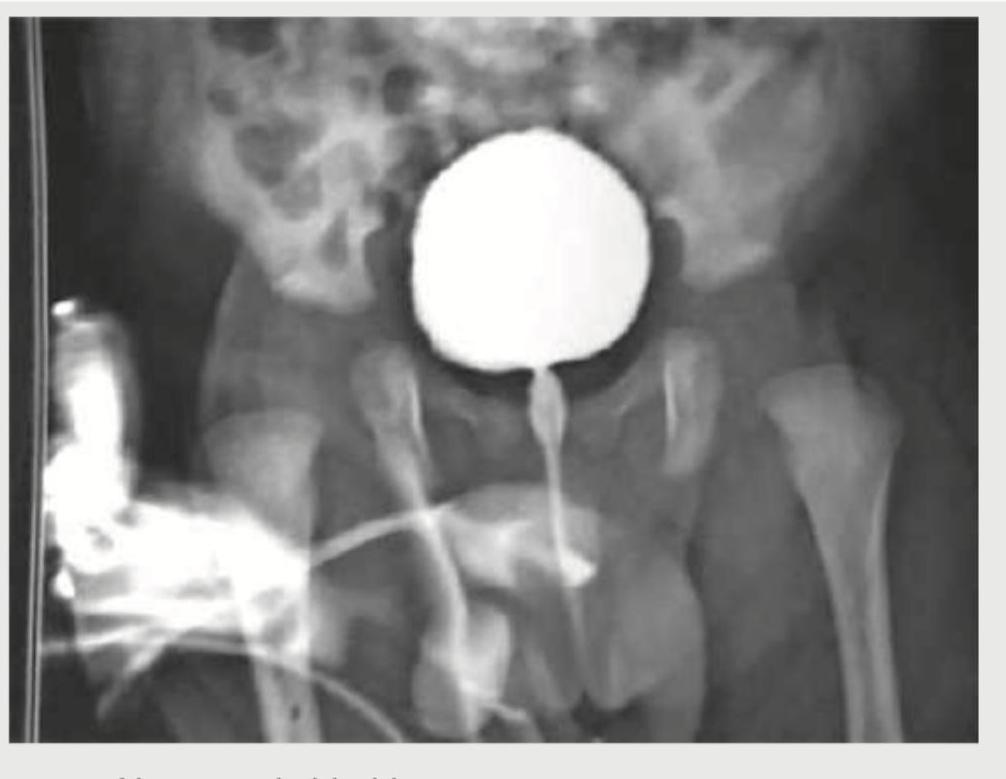

A 1 month old child with recurrent episodes of fever. On examination a suprapubic swelling was noticed and mother reports poor urinary stream. MCUG was performed. All are true about the condition shown except:

Comment on the diagnosis of the image shown below. (AIIMS Nov 2017)

A 3-year-old boy presents with occasional episodes of passing urine after very long durations, going up to as long as 12 hours. Since the child cries due to discomfort and then passes urine with straining, a VCUG is ordered. The VCUG image is shown below. What is the diagnosis?